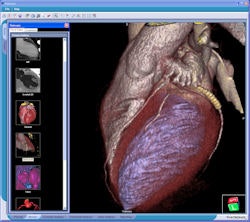

![]() |

| Some specialized clinical applications such as CT cardiac analysis can be made available on a limited number of workstations, making 3D more economical across the healthcare enterprise. Image courtesy of Viatronix. |